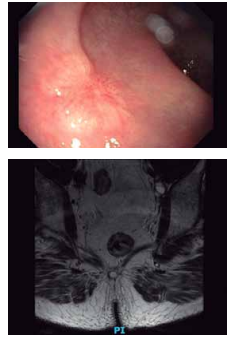

Paciente de 47 anos, assintomática, realiza colonoscopia de rastreamento. É identificada lesão em reto. A biópsia endoscópica é inconclusiva, mas a análise imunohistoquímica mostra positividade para cromogranina A e sinaptofisina.

(Arquivo pessoal; imagens utilizadas com autorização)

O diagnóstico mais provável é: